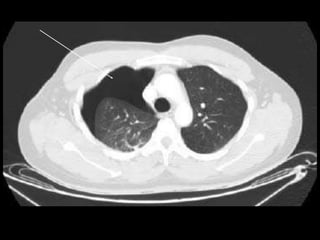

Chest CT scan :-

• Intrapleural gas along with loculated pneumothoraces.

• Pleural effusion, pneumothorax.

RADIOLOGICAL FINDINGS Chest X-ray:- • Hyper translucency between the lung & thoracic cage. • Razor sharp border of the collapsed lung. • Shifting of mediastinum on the opposite side of injury. Chest CT scan :- • Intrapleural gas along with loculated pneumothoraces. • Pleural effusion, pneumothorax. Chest Ultrasound :- • Smooth horizontal echogenic lines are seen above and below the pleural lines. • Absence of lung sliding and B - lines.